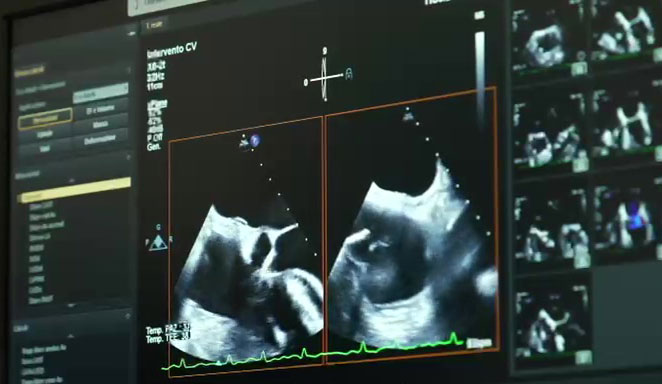

Di recente, l’equipe medica del dott. Bartolomucci per la prima volta in Puglia ha effettuato un intervento di riparazione della valvola mitrale severamente insufficiente, per via percutanea, ossia senza necessità di eseguire una stereotomia, ma attraverso una puntura di una vena periferica, in un paziente di 62 anni, affetto da un grave scompenso cardiaco e severa disfunzione del ventricolo sinistro. Si è trattato di una procedura innovativa di riparazione della valvola mitrale con il supporto di un sistema di assistenza ventricolare chiamato «Impella».